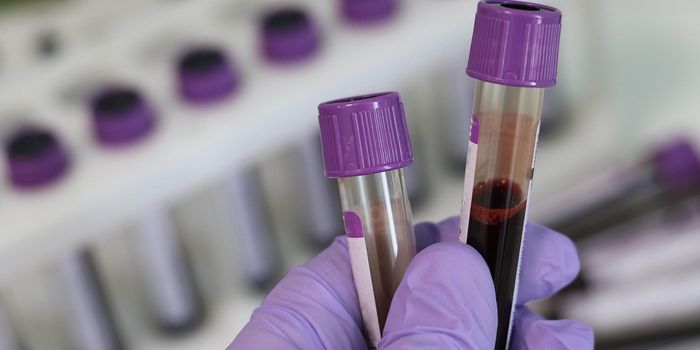

OCT 12, 2021Clinical & Molecular DXScientists have discovered a novel biomarker in the blood that acts as an early warning sign for dementia: microRNA. The ...